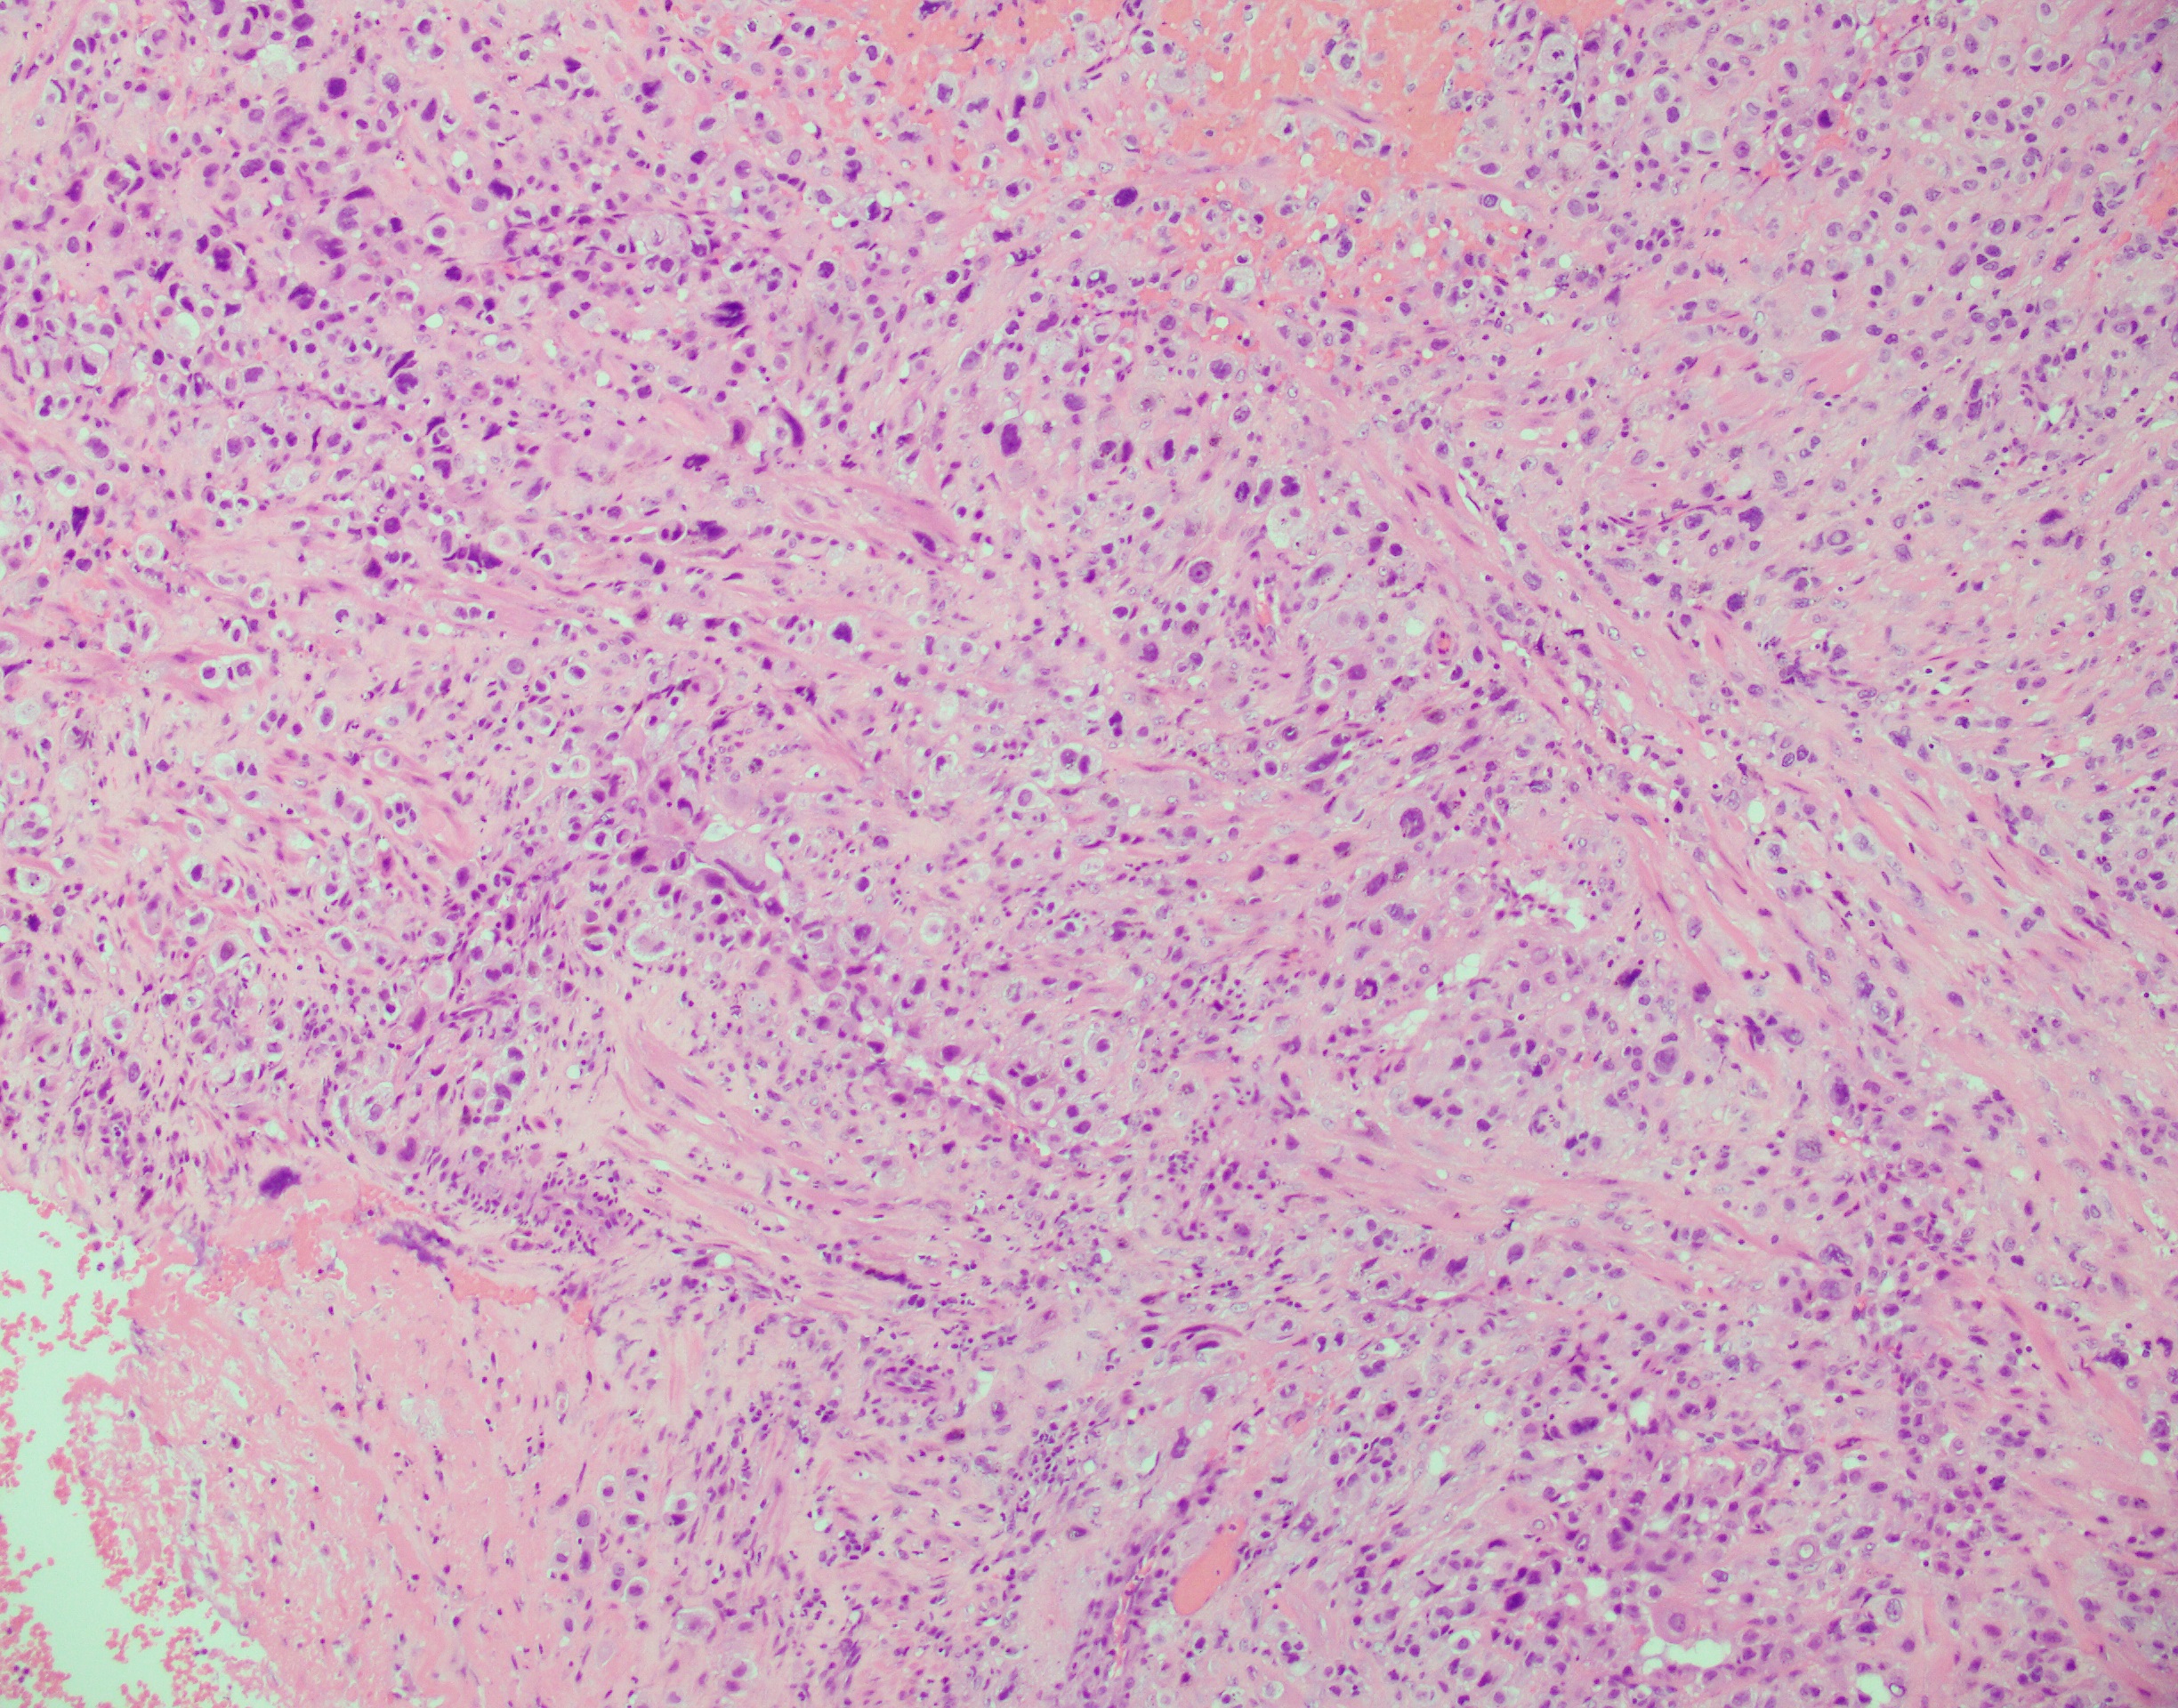

Histologically, the tumor has an infiltrative growth pattern consisting of aggregates or sheets of large, polyhedral to round, predominantly mononucleated cells, with scattered multinucleated cells. The tumor typically infiltrate the myometrium by separating the smooth muscle cells. The cells usually have abundant amphophilic and occasionally eosinophilic or clear cytoplasm. Nuclei are pleomorphic with atypia, large, convoluted and marked hyperchromasia. Most tumors have low mitotic activity. Charactaristic vascular invasion is often present, where tumor cells replace the vessel wall of myometrial vessel.

Top differential diagnosis include exaggerated placental site (EPS), epithelioid trophoblastic tumor (ETT) and gestational choriocarcinoma. EPS would show Ki67 proliferation index 1-5%. ETT has similar histologic features on H&E but stains diffuse positive for p63. Gestational choriocarcinoma would show a Ki67 proliferation index >90%.